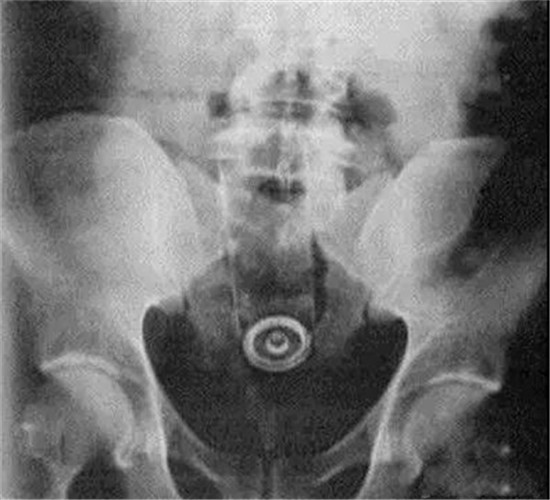

这是一个啤酒瓶。男性。

上面是一个啤酒瓶在大肠里。病人是男性。这是常见的肛门内异物。

这种情况,往往只要给病人打上全身麻醉,肛门松弛后,就可以用卵圆钳经过肛门把啤酒瓶拉出来。